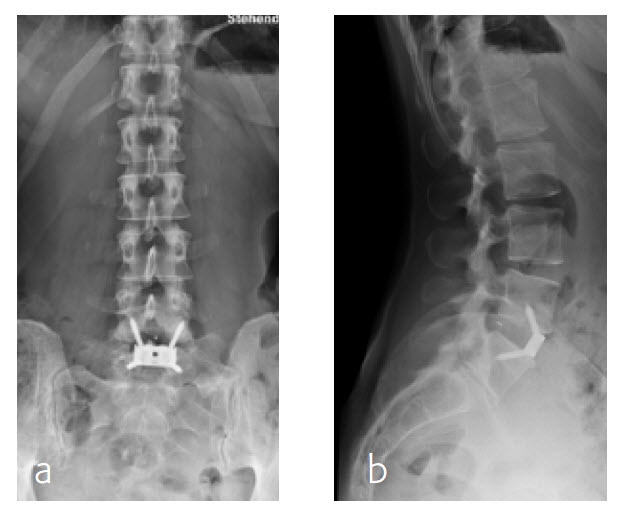

A 47-year-old woman was suffering chronic low back pain for several years, with severe pain attacks and with uncontrolled movements becoming increasingly disabling due to DD and erosive osteochondrosis at L4/L5. Condition after sciatica due to a disc herniation L4/L5, having nonoperative treatment. The MRI findings progressive compared to April 2014 are shown (Fig 5 and 6).

Anterior lumbar interbody fusion surgery was undertaken in July 2016 using the Synfix Evolution with InductOs (6 mg) (Fig 7). Intraoperative: routine operation, no complications. Postoperative: uneventful postoperative course.